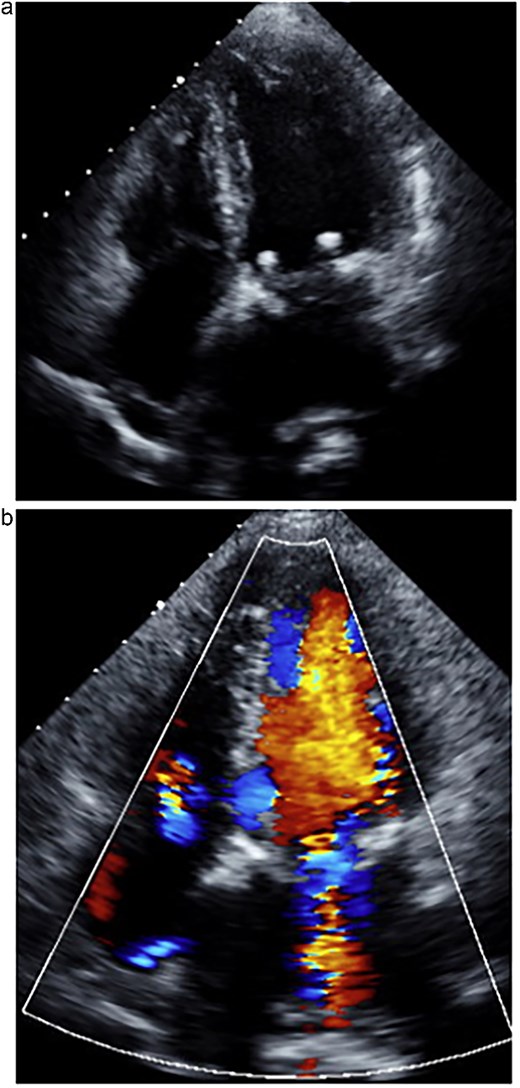

An 80-year-old woman with a history of chronic kidney disease, ulcerative colitis, and dyslipidemia had been followed for severe MR for the past 6 years. She presented with progressive dyspnea and was admitted with acute decompensated heart failure. Transthoracic echocardiography (TTE) demonstrated significant prolapse of the A3 segment and a markedly reduced left ventricular ejection fraction (LVEF) of 30%. Given her frailty, impaired ventricular function, and multiple comorbidities, conventional surgical mitral valve repair was deemed high risk. Therefore, the MitraClip system was selected and performed by the cardiology team. During the MitraClip procedure, however, a posterior mitral leaflet tear occurred, resulting in worsened severe MR (Fig. 1). Consequently, the patient was referred to our department for operation.

Transesophageal echocardiography following the MitraClip procedure. (a) The posterior mitral leaflet is torn, resulting in a loss of continuity. (b) Mitral regurgitation is observed originating from the site of the tear.